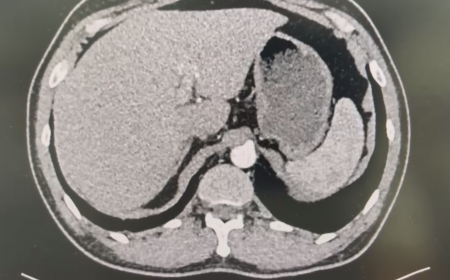

Chụp MRI Có U Ở Gan, Nghi Có Sán Lá Gan

Xin chào Bác sĩ, em ở Hải Phòng, 42 tuổi lâu nay mệt mỏi có triệu chứng sốt nhẹ dài ngày, 4 ngày trước em đi khám và test các bệnh như sốt xuất huyết đều âm...